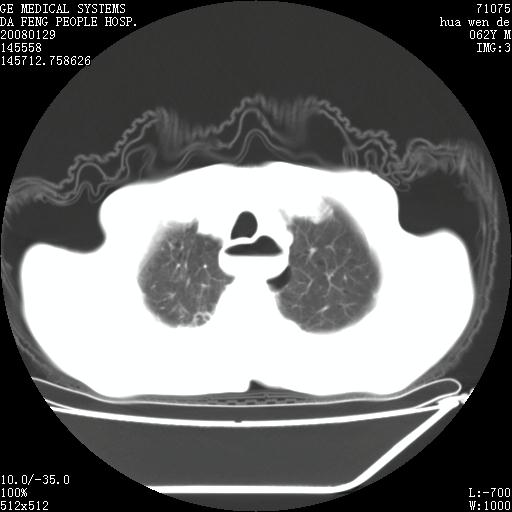

男性,67岁。作肺部检查时发现

考虑:胸腔胃并支气管瘘(并发肺炎,肺脓肿形成)。

理由:1、右上肺内病灶,空洞形成,有液平。

2、肺内多处炎症。

3、前段肺内炎症,支气管引流通畅,与肿块无关系。

1.整个食管扩张,未见明显占位性病变,贲门区亦未见明显占位病变,考虑:贲门失驰缓症;

2.右上肺病变边缘可见毛刺,囊壁厚度不均匀,周围境界较清楚,未见炎性渗出性影,右上肺外带可见片状影,边缘不清,考虑:肺癌伴空洞形成、右上肺炎。

食管全程扩张,壁均匀不厚,喷门失弛缓症

右上肺空洞可见液平,临近肺野磨玻璃密度,考虑1.结核2.脓肿

贲门失驰缓症.肺部感染伴脓肿形成。支持!是否吸入性要结合临床诊断,我们影像是看不出来的。但胸腔胃能排除(1.没有手术史支持,2.双侧胸廓对称,胸壁、肋骨及胸膜规整,3,食管壁明显扩张内壁光滑,胸腔胃黏膜皱襞多较厚)。